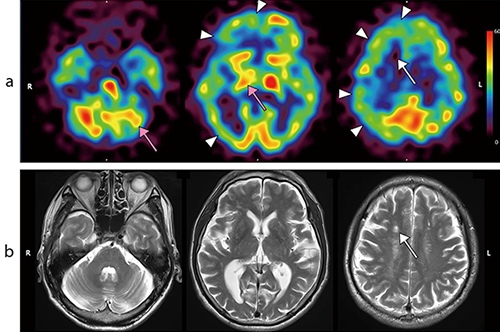

図1 頭蓋内右内頸動脈高度狭窄症

a:123I-IMP 190MBqを用いたARG法による脳血流SPECT定量画像(FANHR、Recon:FBP法、TEW法、Iterative Chang法)

b:頭部MRIのT2強調画像(SPECTから4日後)

約2か月前からの左半身脱力を主訴とする頭蓋内右内頸動脈高度狭窄症の60歳代、男性。SPECT画像では、右半卵円中心の小梗塞巣に一致して高度の血流低下を(a、b ↑)、右前・中大脳動脈領域の広範囲に軽度~中等度の血流低下を認める(a ▶)。右視床と左小脳半球にも軽度の血流低下を認めるが(a ↑)、MRIでは同部位に異常を認めない。これらは脳虚血領域との神経線維連絡を介した遠隔効果を反映している。